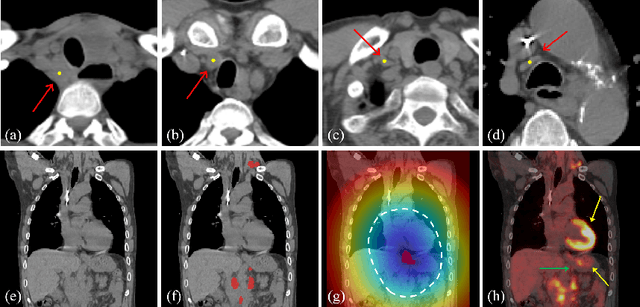

Abstract:Background: The current clinical workflow for esophageal gross tumor volume (GTV) contouring relies on manual delineation of high labor-costs and interuser variability. Purpose: To validate the clinical applicability of a deep learning (DL) multi-modality esophageal GTV contouring model, developed at 1 institution whereas tested at multiple ones. Methods and Materials: We collected 606 esophageal cancer patients from four institutions. 252 institution-1 patients had a treatment planning-CT (pCT) and a pair of diagnostic FDG-PETCT; 354 patients from other 3 institutions had only pCT. A two-streamed DL model for GTV segmentation was developed using pCT and PETCT scans of a 148 patient institution-1 subset. This built model had the flexibility of segmenting GTVs via only pCT or pCT+PETCT combined. For independent evaluation, the rest 104 institution-1 patients behaved as unseen internal testing, and 354 institutions 2-4 patients were used for external testing. We evaluated manual revision degrees by human experts to assess the contour-editing effort. The performance of the deep model was compared against 4 radiation oncologists in a multiuser study with 20 random external patients. Contouring accuracy and time were recorded for the pre-and post-DL assisted delineation process. Results: Our model achieved high segmentation accuracy in internal testing (mean Dice score: 0.81 using pCT and 0.83 using pCT+PET) and generalized well to external evaluation (mean DSC: 0.80). Expert assessment showed that the predicted contours of 88% patients need only minor or no revision. In multi-user evaluation, with the assistance of a deep model, inter-observer variation and required contouring time were reduced by 37.6% and 48.0%, respectively. Conclusions: Deep learning predicted GTV contours were in close agreement with the ground truth and could be adopted clinically with mostly minor or no changes.